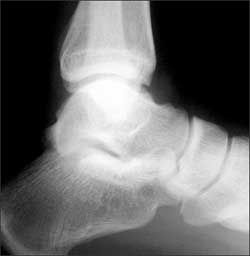

(Answer on next page.)Right ankle pain after a basketball injury: The frontal view of the ankle reveals soft tissue swelling that is predominantly lateral (A, yellow arrow). A small ossific fragment is evident distal to the lateral malleolus (A, white arrow); close inspection shows this to be well-corticated. The remainder of the osseous structures are intact. The lateral view reveals a joint effusion in the talotibial joint (B, arrow); no fractures are visible. In the oblique view (C), the osseous structures appear intact.

The well-corticated ossific fragment is consistent with an old injury, but it is in the region that is now extremely tender. The joint effusion indicates that the current injury is severe. However, this is a nonspecific finding; joint effusions are seen with fractures and ligament and tendon injuries.